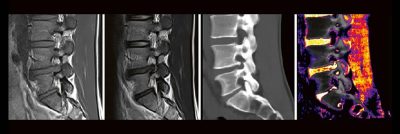

Categories: WebinarDual-Energy CT der Wirbelsäule: Technik und klinische Praxis (Webinar | Online)

Professor Dr. med. Matthias PumbergerPD Dr. med. Torsten Diekhoff Die Dual-Energy-Computertomographie (DECT) hat für viele klinische Anwendungen bereits Einzug in die Praxis genommen. Für die Behandlung von Wirbelsäulenerkrankungen sind besonders die Darstellung von Knochenmarkveränderungen (z. B. bei osteoporotischen Frakturen) und der Bandscheibe (z. B. bei Bandscheibenvorfällen) interessant und werden intensiv beforscht. Hierdurch versprechen wir uns eine schnellere Therapie für unsere […]